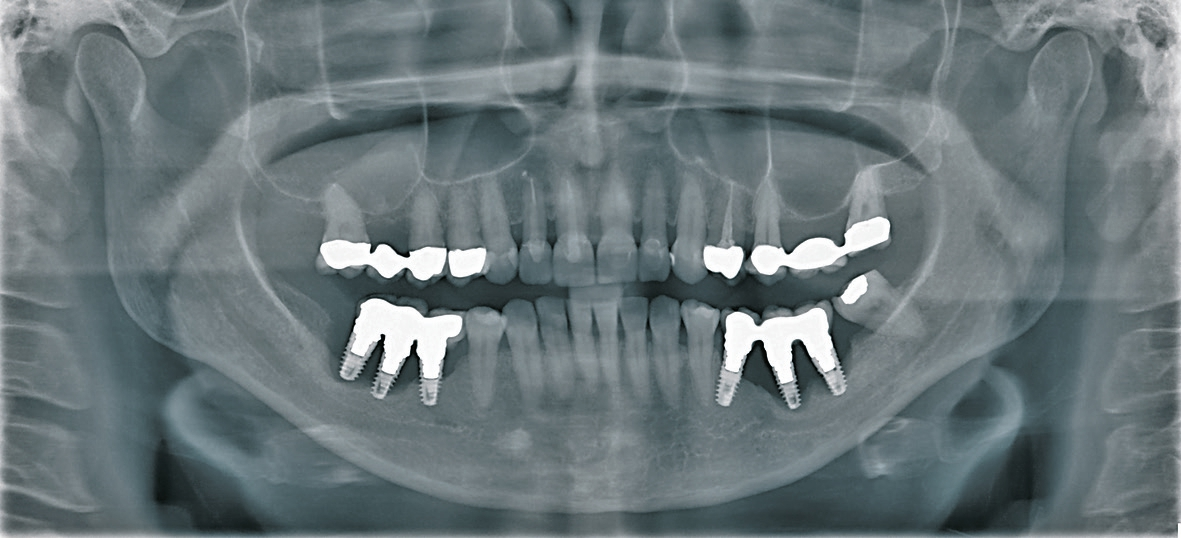

Uns treibt angesichts dessen die Frage um: Wie langlebig und verträglich sind die Neu- und Weiterentwicklungen für den Patienten? Welchen Nutzen als Zahntechniker habe ich und welche Risiken gehe ich ein? Soll ich beim Bewährten bleiben oder lieber zukunftsorientiert jedem Trend – oder wenigstens einem Teil davon – folgen? Nach mittlerweile 37 Jahren Berufserfahrung in der Zahntechnik drängt sich mir die Frage auf, ob tatsächlich alles und jeder „Fortschritt“ sinnvoll und zum Wohle des Patienten ist. Gerade in der Implantatprothetik stellen sich Misserfolge (Abb. 1 und 2) bei Unkenntnis oder Missachtung von fundierten Studien und Praxiserfahrungen ein.

Die hier besprochene 62 Jahre alte Angstpatientin war bereits längere Zeit nicht mehr in Behandlung. Erst als sich die Mundsituation unerträglich verändert hatte und das Kauen sehr stark beeinträchtigt war, entschloss sie sich, beim Zahnarzt vorstellig zu werden. Im Oberkiefer zeigte sich, dass sie eine insuffiziente Keramikbrücke auf sechs Restpfeilern (Zähne 15, 13, 22, 24, 26) hatte. Diese Brücke war zwischen 22 und 23 gebrochen (Abb. 46). Alle Zähne im Oberkiefer waren stark gelockert und teilweise samt der Brückenkonstruktion gewandert, sodass eine Rekonstruktion der ursprünglichen Zahnstellung nicht mehr möglich war. Im Unterkiefer bestand der vorhandene Zahnersatz aus einer über 10 Jahre alten, ständig erweiterten, ebenfalls insuffizienten Teleskopprothese auf zwei Wurzelresten der Zähne 33 und 44.